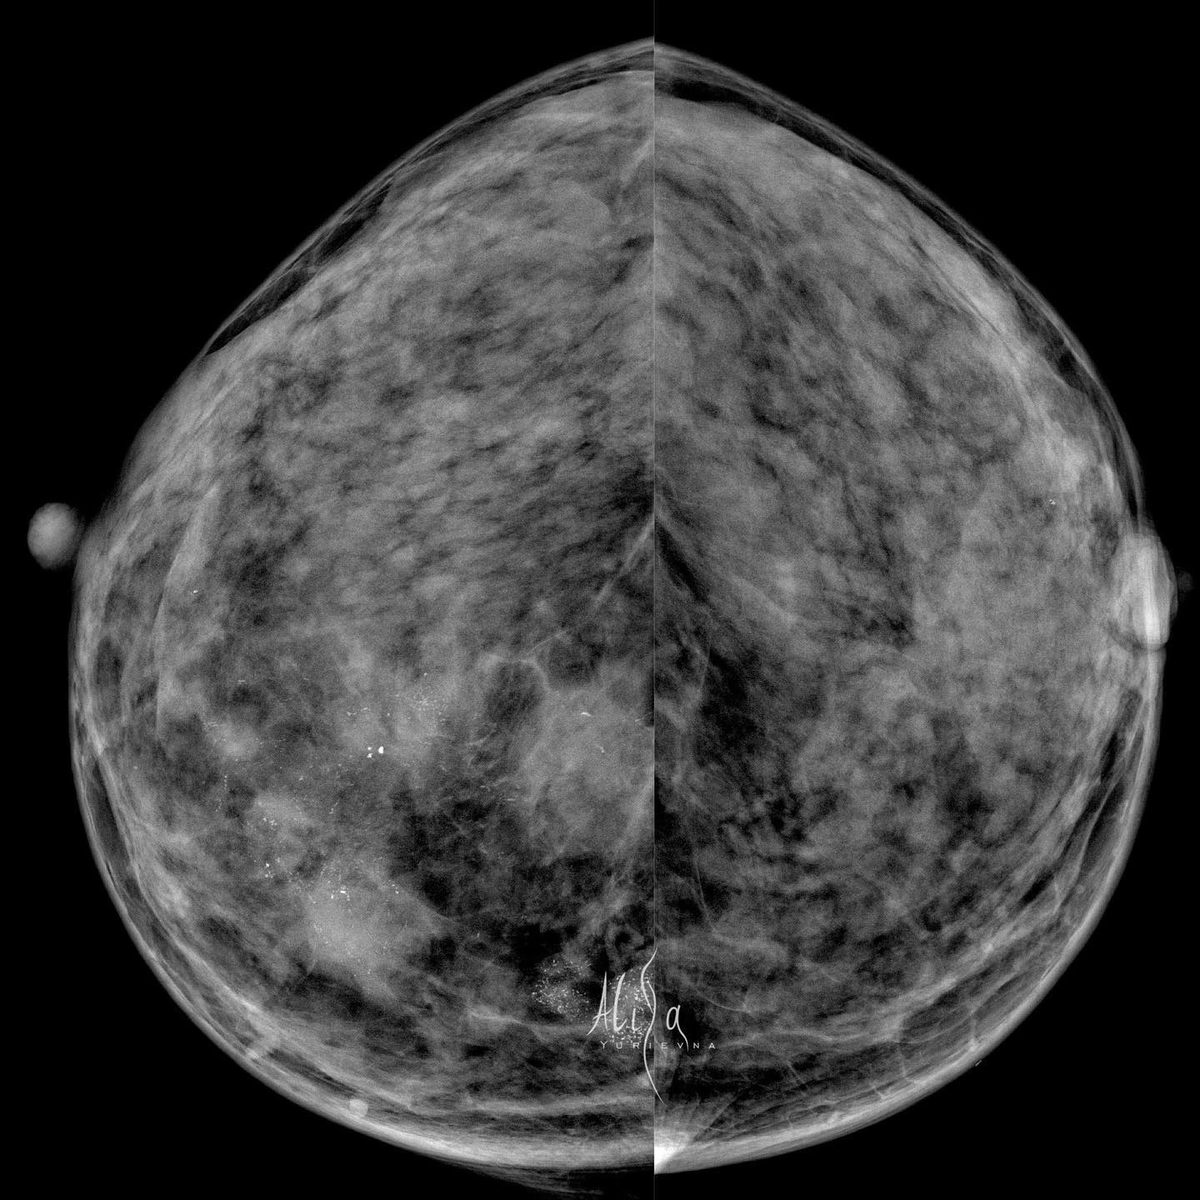

Женщина 38 лет

Инвазивная карцинома молочной железы, неспецифицированная, G2. ER 8 баллов, PR 4 балла, HER2/neu 1+, Ki67 ~ 30%

P.S: с точки зрения рентгенологии тут, конечно, глаз радуется от разнообразия проявлений